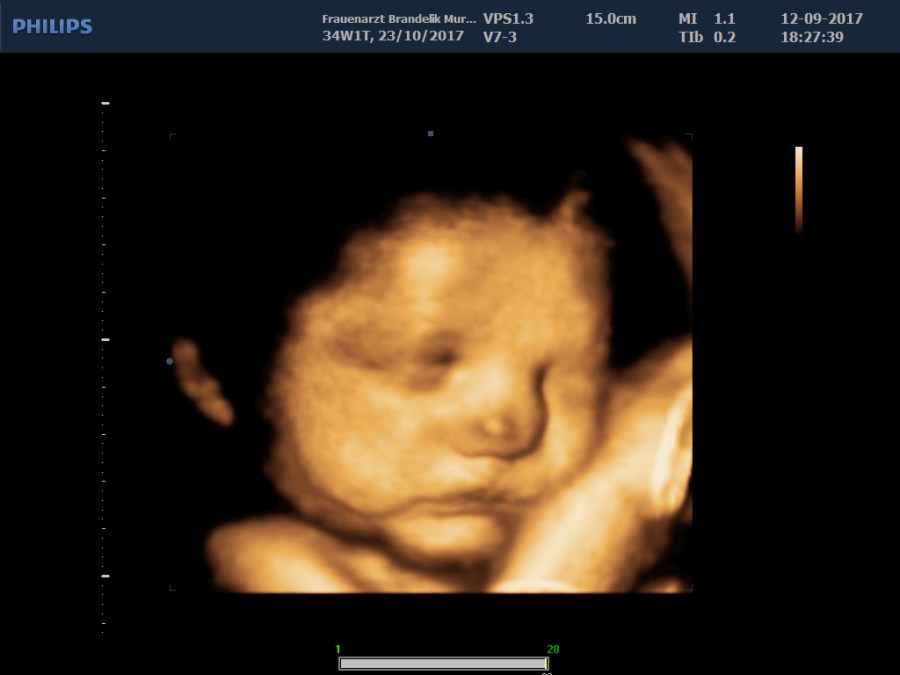

Kinderwunsch und Schwangerschaft zählen zu den bedeutsamsten Phasen im Leben der Frau. Ich führe alle Untersuchungen gemäß den aktuellen Mutterschaftsrichtlinien durch. Darüber hinaus besteht auch die Möglichkeit des 3D/4D Ultraschalles und der Messung des Blutflusses (Dopplersonographie) auf Wunsch. Für Ihre Fragen habe ich immer ein offenes Ohr. Bei Kinderwunsch und ungewollter Kinderlosigkeit berate ich Sie persönlich und unterstütze Sie bei der Suche möglicher Ursachen in Zusammenarbeit mit Hormonspezialisten, Urologen und Kinderwunschzentren.